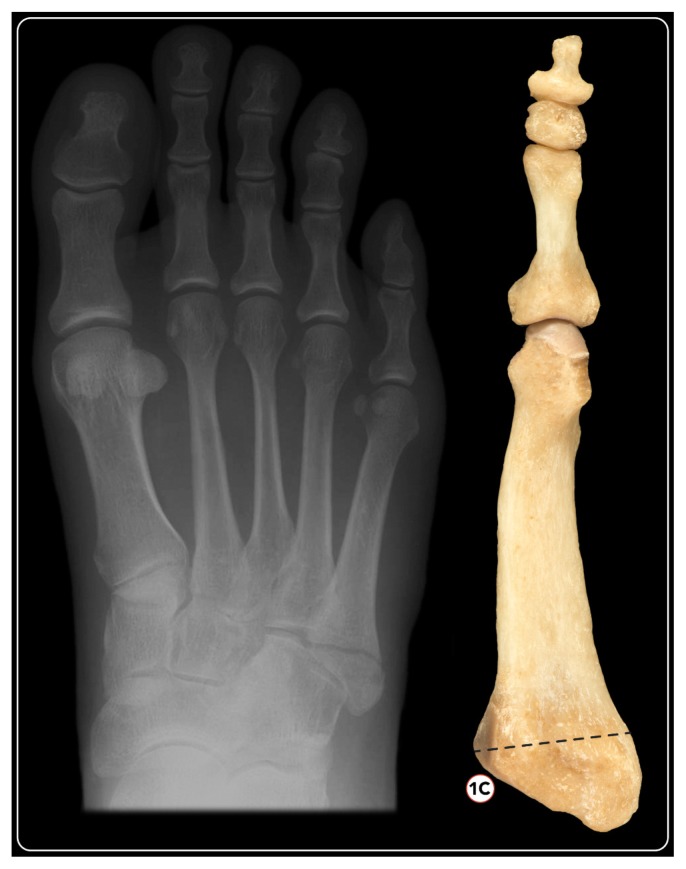

Type-1b: fracture involving the middle one-third metatarsal-cuboid joint (Fig. 4);

Type-1c: fracture involving the medial one third metatarsal-cuboid joint (Fig. 5);

Figure 5.

X-ray of a Type-1c fracture and correlation in bone model: fracture involving the medial one third metatarsal-cuboid joint.